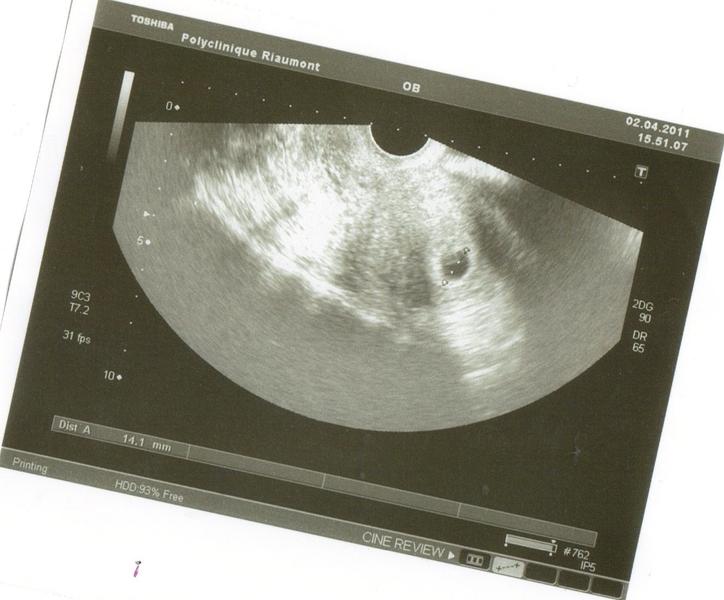

ouai jai u une echo samedi jai juste entendu le batement du coeur mais sur lecho on voi rien le gygy ma di que c petit encor pour voir

jvien de capté que sur lécho le gygy a meme pa noté mon nom mdrrrr

jte montre lécho

dsl la photo est pa droite les scanner ve pa la fair autremen mdrrrrr

Pièces jointes

• 02-04-2011 20;22;17.jpg

02-04-2011 20;22;17.jpg

43.2 KB · Affichages: 86